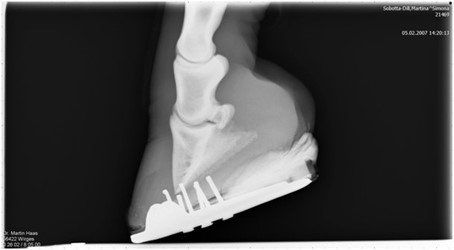

Erstes Anzeichen ist eine auf der Sohlenseite sichtbare Trennung zwischen Sohle und Wand. Wenn man aus diesem Spalt das angesammelte Material entfernt und näher betrachtet, findet man Schmutz und zerfallenes Horn, das Zersetzungsprodukt der Destruenten. Die Zusammenhangstrennung kann sich bis zum Kronsaum erstrecken und ist in ihrem Ausmaß durch eine Röntgenaufnahme feststellbar. Bei vorsichtigem Abklopfen der Hornwand klingen die betroffenen Bereiche hohl. In chronischen Fällen zeigt sich am proximalsten Punkt der Infektion eine Ausbuchtung der Wand nach außen. Wie bei allen Pilzinfektionen der Hufwand ist ein charakteristischer fauliger Geruch vorhanden.

Zur Lahmheit führt White Line Disease bei rechtzeitiger Erkennung in der Regel nicht. Erst wenn ein Drittel oder mehr der tragenden Huffläche betroffen ist, wird das Pferd lahmen. Ist der Zehenbereich stark befallen, kann es zu einer Rotation des Hufbeines kommen. Eine Röntgenaufnahme gibt dann Aufschluss über die Hufbearbeitung und den Beschlag.

Auf der Röntgenaufnahme wird unter Verwendung eines Kontrastmittels die Trennung der Wand in Form von kanalförmigen Aufhellungen sichtbar. Dies stellt auch die Grundlage für die Tiefe der betroffenen Bereiche nach proximal und den Umfang der Wandresektion dar.

Nach der Wandresektion und des sorgfältigen Reinigens der freigelegten sensiblen Bereiche konnte über den möglichen Beschlag nachgedacht werden. Als klar war, dass der äußere Zehennagel gesetzt werden konnte, fiel die Wahl auf einen Eisenbeschlag. Da die Wand um mindestens ein Drittel entfernt worden war, mussten sowohl Strahl als auch Sohle zum Mittragen einbezogen werden. Ich entschied mich für eine Art Herzeisen und eine Füllung mit einem Polyurethanpolster (Equi-Build von Vettec).